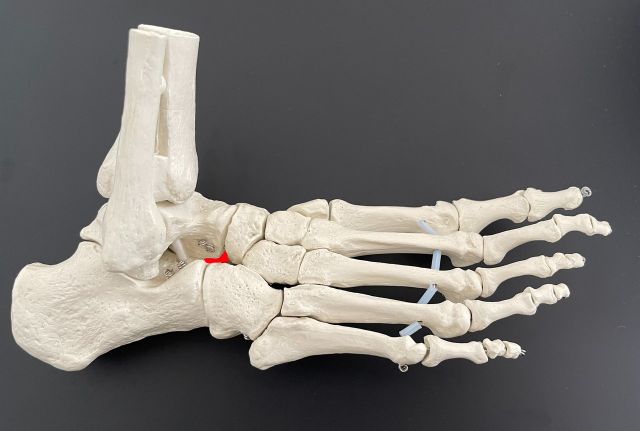

Sind beide Bandanteile defekt, werden beide durch ein Kunstband ersetzt.

Dieses wird dann an Stelle der ursprünglichen Bandstrukturen eingebracht und in eigens gebohrten Knochentunneln mittels Implantaten fixiert.P ostopertiv ist die Verwendung einer Sprunggelenksschiene und für 3 Wochen die Verwendung von Unterarmstützkrücken notwendig.